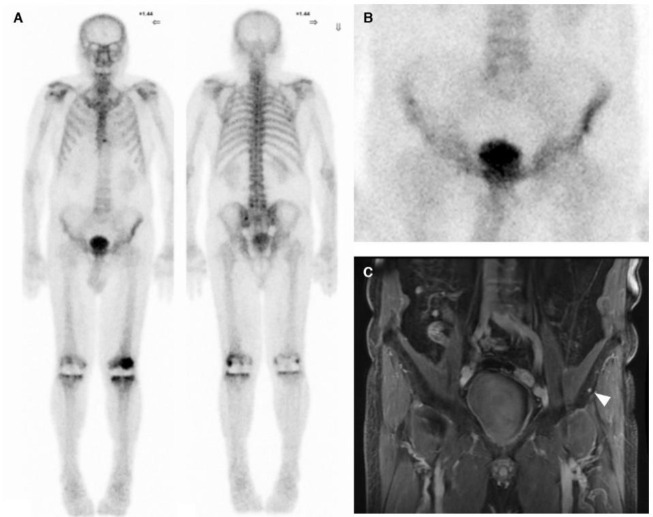

Abstract Image